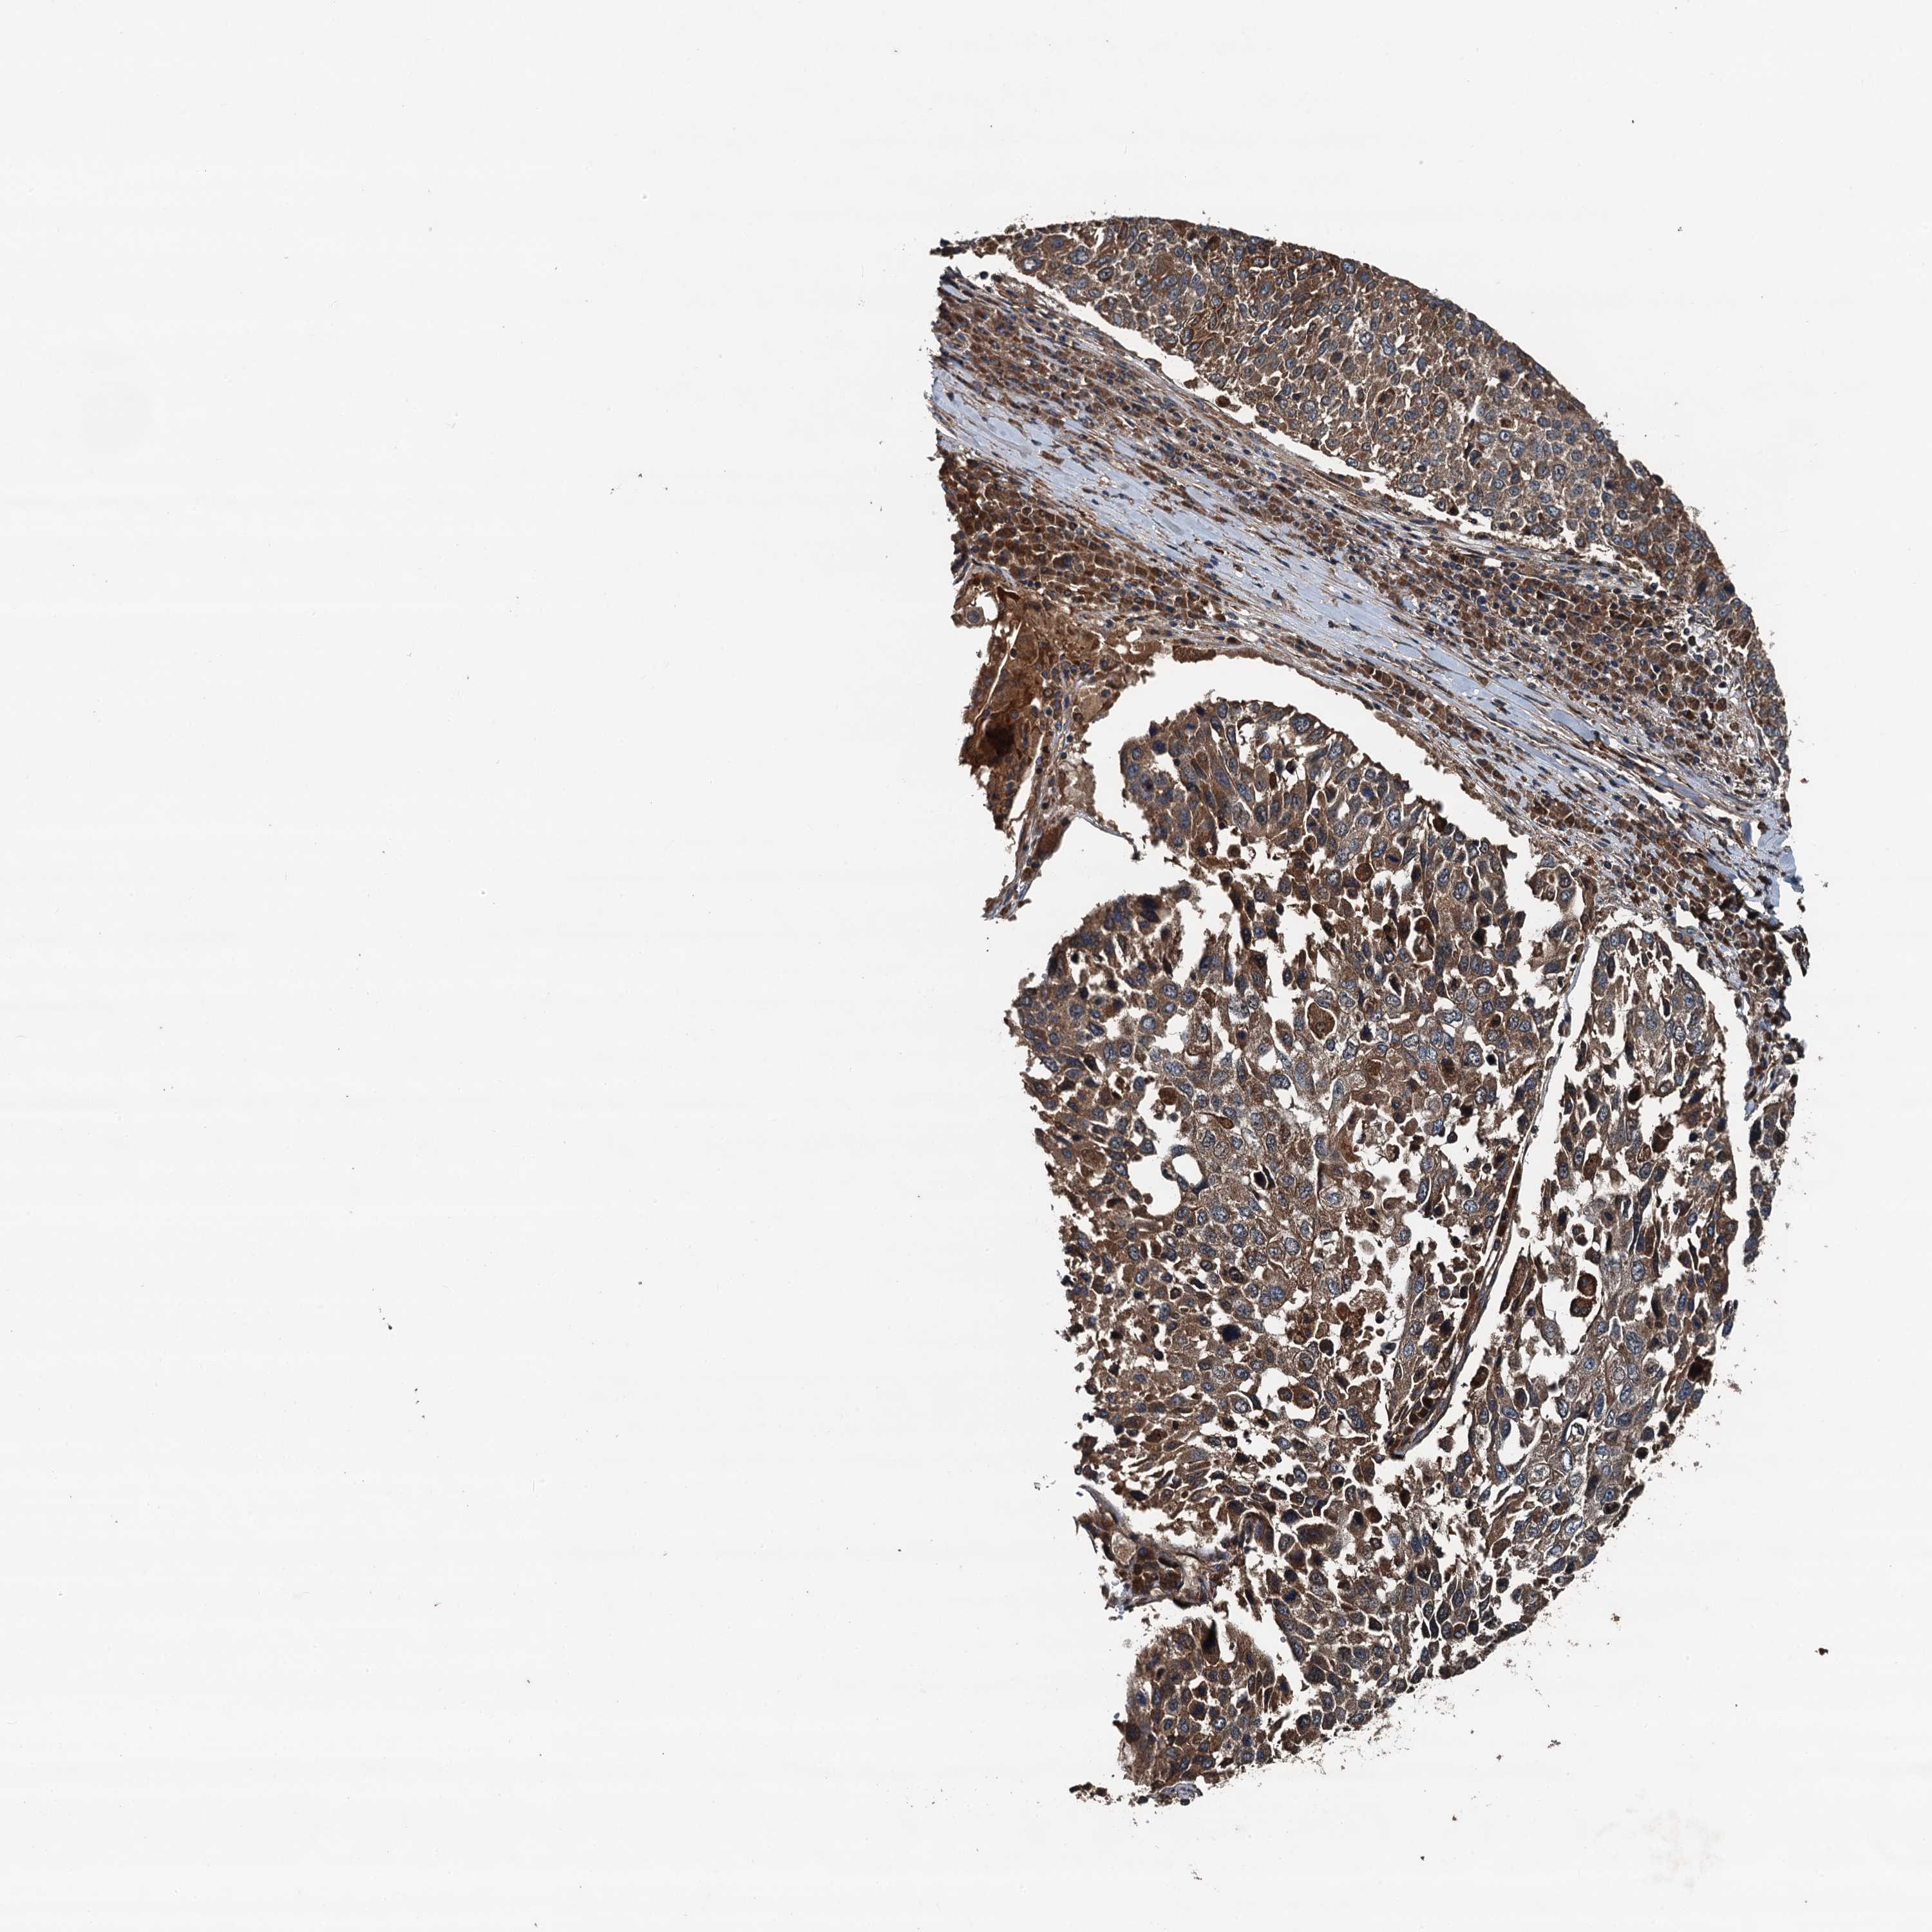

CANCER LUNG CANCER Show tissue menu

Lung cancer

Human cancer

Lung adenocarcinoma